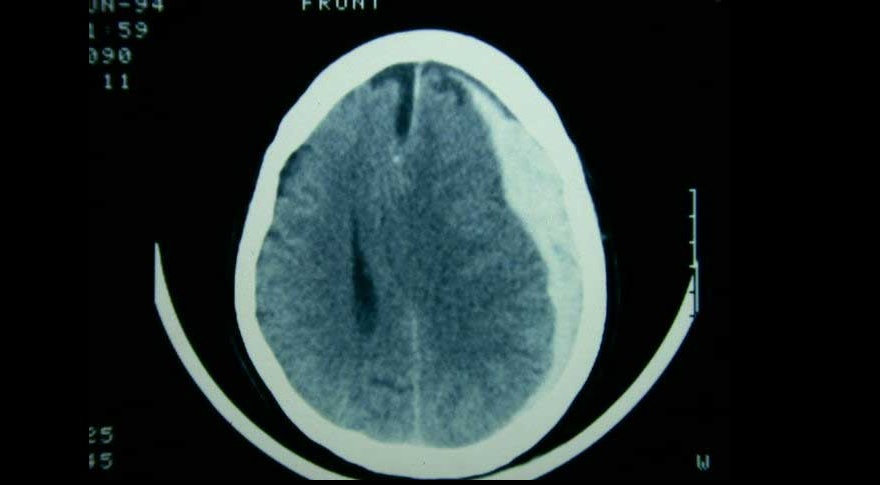

Embolización de la arteria meníngea media en el hematoma subdural subagudo o crónico

Tres ensayos clínicos exploran la utilidad de la embolización de esta arteria en el manejo del hematoma subdural subagudo o crónico, con miras a reducir la tasa de recurrencias y la necesidad de nuevas intervenciones. New England Journal of Medicine, 20 de noviembre de 2024.